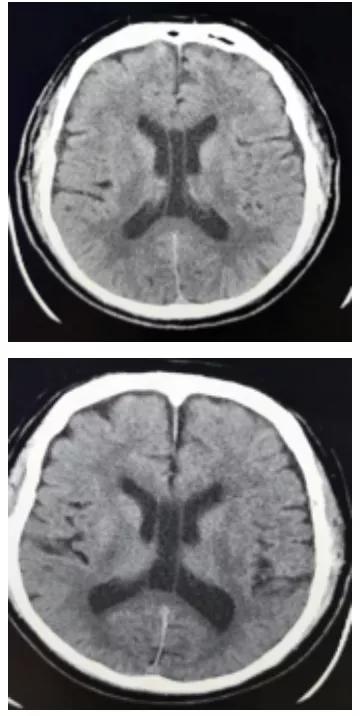

透明隔腔(CSP) 的前上方为胼胝体,后下方为穹隆。侧壁即透明隔小叶。透明隔腔≤3mm,描述可见透明隔腔。

1.胼胝体膝部;2.透明隔腔;3.穹隆柱;4.穹隆体;5.穹隆脚;6. Vergae腔;7.胼胝体压部

透明隔腔增宽是透明隔腔≥3mm,直径<10mm,描述可见透明隔腔增宽,透明隔的两壁呈前后平行排列,边界清晰,或内凹,对周围组织无压迫,为正常生理变异,临床无症状。透明隔腔≥10mm,描述可见透明隔腔明显增宽。